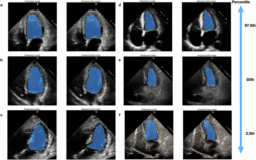

![]() | Foundation versus domain-specific models for left ventricular segmentation on cardiac ultrasoundnpj Digital Medicine - (Friday June 6, 2025) - Frequent Updates / npj Digital Medicine | |||